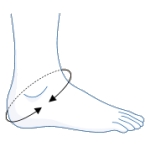

• ActyFoot is designed to provide support, stabilization and partial immobilization (restriction of movement) of the ankle

• Three integrated straps provide proprioceptive feedback and work together with semi-rigid elements to stabilize the ankle and restrict excessive range of movement

• Cross strap further helps minimize the risk of ankle inversion